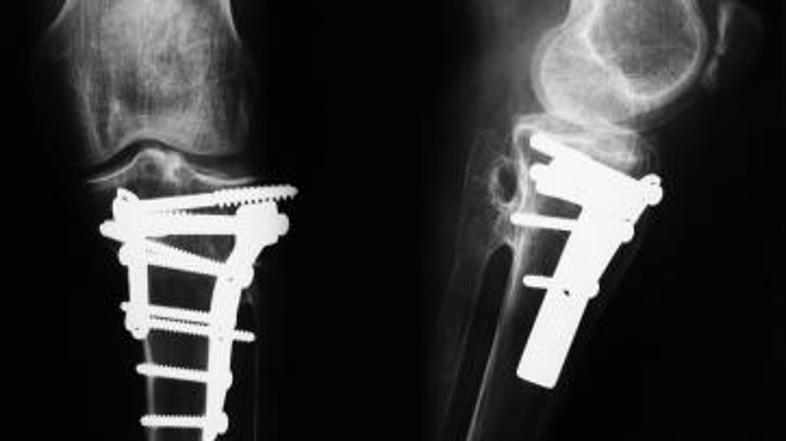

Z leti pa je bila bolečina vedno hujša. Pred kratkim se je tako odločil, da gre znova v bolnišnico. Rentgenska slika je presenetljivo pokazala, da se tri kosti niso pravilno zarasle.